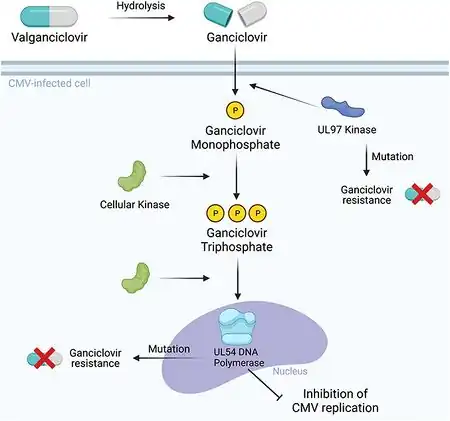

Ganciclovir is a synthetic analogue of 2′-deoxy-guanosine. It is first phosphorylated to ganciclovir monophosphate by a viral kinase encoded by the cytomegalovirus (CMV) gene UL97 during infection. Subsequently, cellular kinases catalyze the formation of ganciclovir diphosphate and ganciclovir triphosphate, which is present in 10-fold greater concentrations in CMV or herpes simplex virus (HSV)-infected cells than uninfected cells.

Ganciclovir triphosphate is a competitive inhibitor of deoxyguanosine triphosphate (dGTP) incorporation into DNA and preferentially inhibits viral DNA polymerases more than cellular DNA polymerases. In addition, ganciclovir triphosphate serves as a poor substrate for chain elongation, thereby disrupting viral DNA synthesis by a second route.

- Valganciclovir, the prodrug of ganciclovir